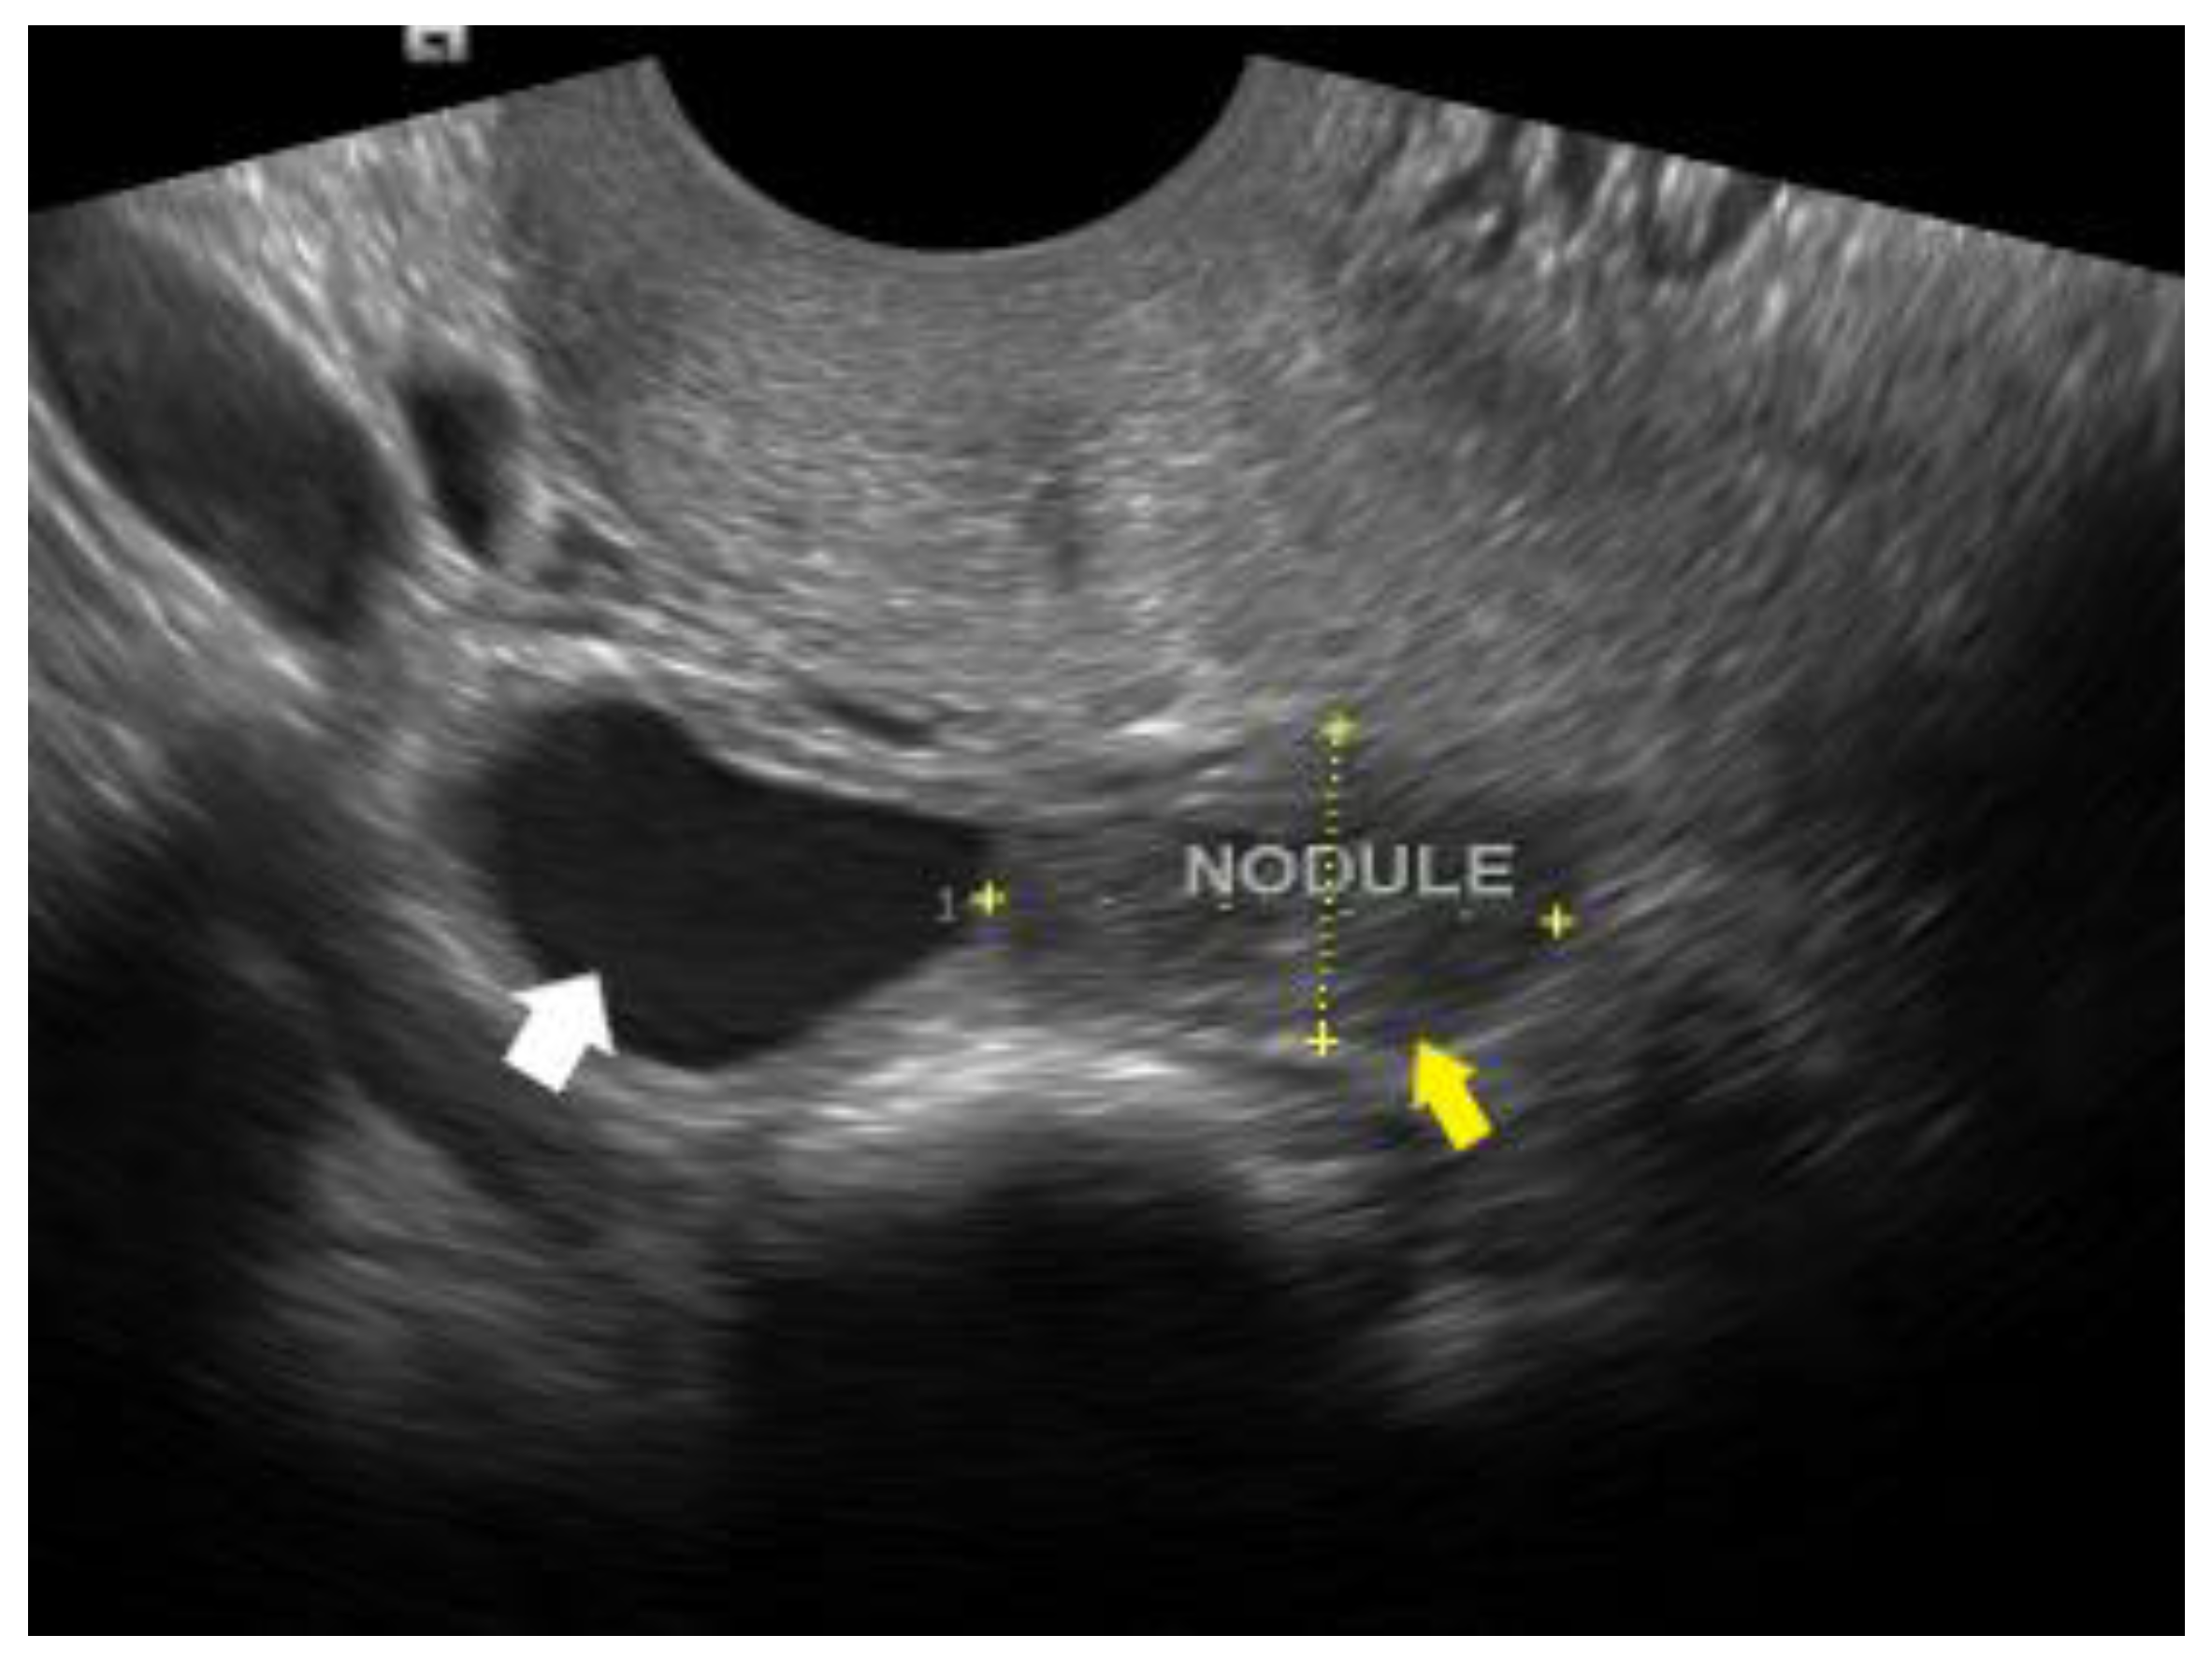

2.6.2. Rectum and Sigmoid Colon

- Guerriero, S.; Ajossa, S.; Orozco, R.; Perniciano, M.; Jurado, M.; Melis, G.B.; Alcazar, J.L. Accuracy of transvaginal ultrasound for diagnosis of deep endometriosis in the rectosigmoid: Systematic review and meta-analysis. Ultrasound Obstet. Gynecol. 2016, 47, 281–289. [Google Scholar] [CrossRef] [PubMed]

- Gerges, B.; Li, W.; Leonardi, M.; Mol, B.W.; Condous, G. Optimal imaging modality for detection of rectosigmoid deep endometriosis: Systematic review and meta-analysis. Ultrasound Obstet. Gynecol. 2021, 58, 190–200. [Google Scholar] [CrossRef] [PubMed]